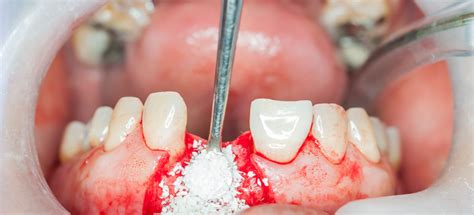

- Procedimiento quirúrgico: se realiza una incisión en las encías, se coloca el injerto y se cierra la zona tratada. El tratamiento para la colocación del injerto de hueso dental se realiza bajo sedación y anestesia local.

Llegada la fecha de la operación, sus manos expertas han de efectuar un corte en la zona donde debe ir el injerto. A continuación, se coloca una membrana que cubre la operación y que impide que se pierda el implante, y se cose la encía.